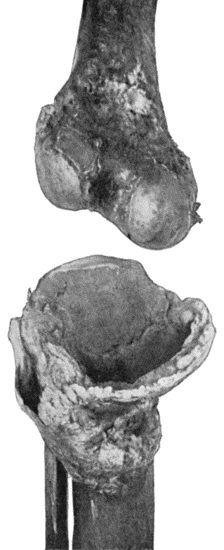

| 162. | Bones of Knee in Charcot's Disease | 533 |

| 163. | Charcot's Disease of Left Knee | 534 |